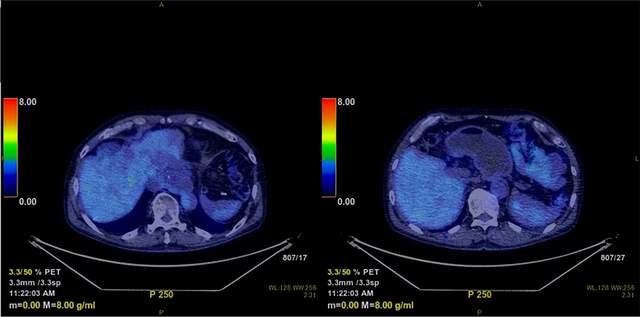

典型案例治疗进度图: